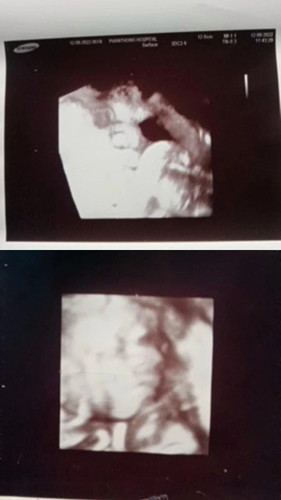

#ท้องแรกคะ กำหนดคลอด28 ก.ย เปรียบเทียบรูปภาพอันตราซาวค่ะ รูปข้างบนซาวตอน37+5วีคค่ะ รูปข้างล้างซาวตอน22+5วีคค่ะ(รูปภาพข้างบนที่พึ่งซาวตอน37+5 คือส่วนใหนของน้องหรอค่ะหนูดูไม่ออกเลยค่ะ มีแม่ๆคนใหนดูออกบ้างมั้ยคะ🙏❤️ตอนนี้กังวนค่ะดูแบบใหนก้ดูไม่ออกเลย แม่ๆช่วยดูให้หน่อยได้มั้ยค่ะ🙏👶🥰#ขอบคุณล่วงหน้านะคะ❤️🙏